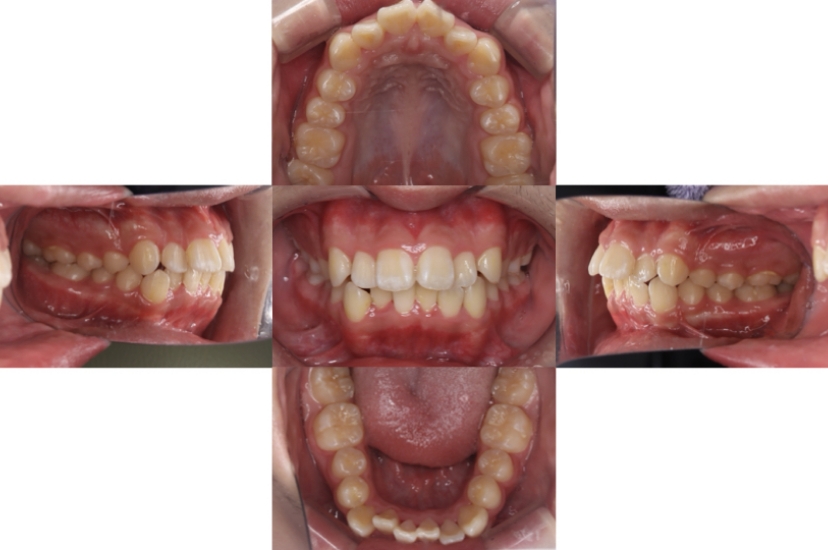

BEFORE

AFTER

上下顎前突、叢生(上下出っ歯、上下の前歯のガタガタ)のケースです。

装置はラビアル(上下表側)で、上下顎の小臼歯を4本抜歯を行っています。抜歯したスペースを使って、上下の前歯の後方移動と叢生(ガタガタ)の改善を行っています。

主訴 前歯のガタガタと口元がでているのが気になる。

年齢・性別 30歳 女性

お住まいの地域 東京都大田区

治療方針 抜歯スペースを利用して上前歯の叢生(ガタガタ)と口元突出の改善

抜歯部位 上下顎左右第一小臼歯

使用装置 ラビアル(上下表側)、顎間ゴム

治療期間 1年11か月

治療回数 13回

リテーナー クリアリテーナー